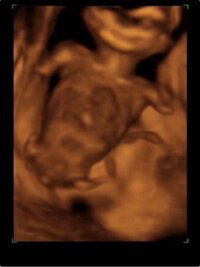

エコー写真で男の子・女の子の性別の見分け方をみていきましょう。 女の子の特徴 木の葉型・コーヒー豆がみえる 週数が経つと外性器が形成され、股の部分に割れ目がエコーで見えるでしょう。 この割れ目が女の子の外性器です。 三本線やコーヒー豆などと表現されることもあります。 男の子と同じように、突起物で性別を判断することはできません。 女の子のエコー写真の特徴3:子宮 女の子のエコー写真の特徴3つめは、子宮です。女の子エコー木の葉写真 エコー写真(赤マルの所)を見て女の子、男の子のどちらだと思いますか? 右上が妊娠14週のもので、男の子のシンボルのようにも見えますが、この時まだどっちかわからないと言われ、左下の妊娠18週の頃にたぶん女の子か 女の子のエコー写真の特徴 女の子の判別する

女の子は男の子特有のシンボルが足の間にはなく、外陰部らへんに女性の大陰唇と分かる割れ目が見えると女の子 男の子の場合は、お股の間にピーナッツのような突起物 2d、3d、4dエコー妊娠25週目の女の子のエコー写真 こちらは25周目の女の子のエコー写真。 右側がおしり、左側が足です。 おまた部分を見てみるとコーヒー豆のようなシンボル等は見えないものの、明らかな突起物などもありません。 16週 エコー 突起物 女の子 エコー写真から性別判定お願いします 妊娠28週です 担当の先生には男 こちらの記事に対するkozokaeruさんのコメントです 胎児 エコー 女の子 割れ目女の子 エコー 木の葉 写真女の子 エコー 突起物 画像エコー写真 男の子 女の子 違「女の子で間違いないですね~^^」 っ